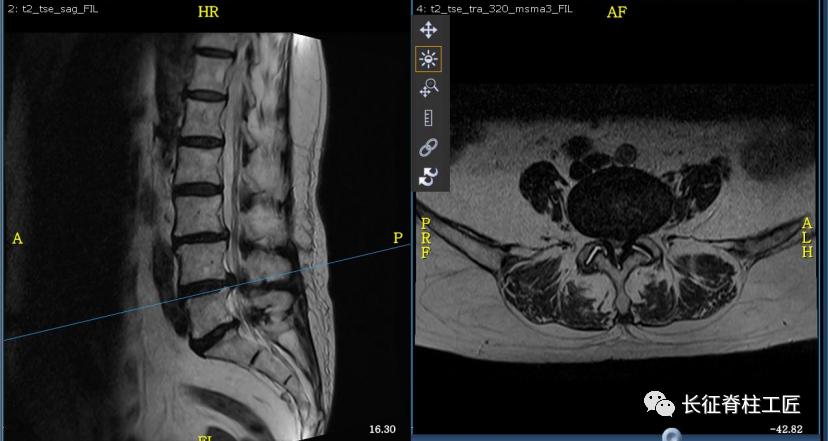

入院检查,腰部疼痛,后伸时加剧,局部压痛,双下肢肌力减退。X线检查,L4、L5骨质增生,MRI显示L4/L5、L5/S1椎间盘突出,马尾神经受压明显,被确诊为腰椎管狭窄症。

马尾神经综合征早期表现为会阴部麻木、感觉减退。当出现大小便功能障碍时,提示神经功能已经严重损害,应该立即采取急诊减压手术治疗,解除对马尾神经的压迫,尽可能挽救马尾神经功能。